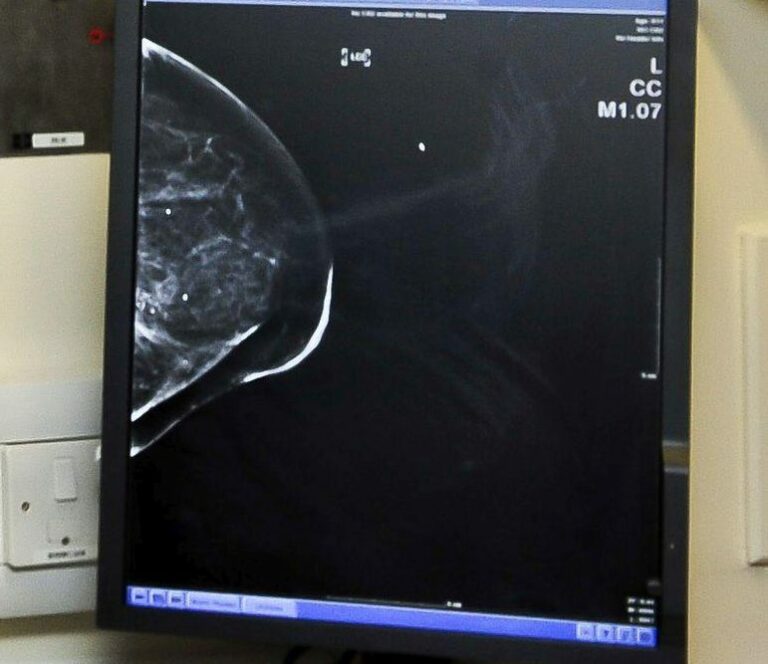

Tumore al seno, Fda approva un nuovo farmaco di Menarini

MILANO (ITALPRESS) – La Food and Drug Administration (FDA) degli Stati Uniti ha approvato la molecola elacestrant (ORSERDU) per il trattamento di un sottotipo di cancro al seno avanzato o metastatico.

Si tratta di un degradatore selettivo del recettore degli estrogeni (SERD) per il trattamento di donne in post-menopausa e di uomini adulti con carcinoma mammario avanzato o metastatico, positivo per il recettore degli estrogeni (ER+) e negativo per il recettore HER2-, che abbiano sviluppato mutazioni di ESR1, dopo almeno una di linea di trattamento con terapia endocrina.

“E’ il primo e unico SERD a somministrazione orale ad aver completato con successo l’ultimo step dello sviluppo clinico (fase III) e ad essere approvato da un’autorità regolatoria”, si legge in una nota.

Il farmaco sarà disponibile negli Stati Uniti tramite Menarini Stemline, azienda biofarmaceutica acquisita dal Gruppo Menarini nel 2020.

“L’approvazione di ORSERDU (elacestrant) da parte dell’FDA rappresenta la prima terapia in assoluto per i pazienti con carcinoma mammario ER+/HER2- avanzato o metastatico con mutazioni ESR1 e siamo molto orgogliosi di poter offrire una terapia target che possa soddisfare questo grande bisogno terapeutico irrisolto”, ha commentato Elcin Barker Ergun, Amministratore Delegato del Gruppo Menarini. “Siamo grati ai pazienti, agli investigator e agli administrator che hanno partecipato agli studi clinici che hanno portato a questa straordinaria innovazione”, aggiunge.

Elacestrant è stato approvato da FDA con la procedura di Priority Review e Fast Track sulla base dei risultati dello studio registrativo di fase III EMERALD.